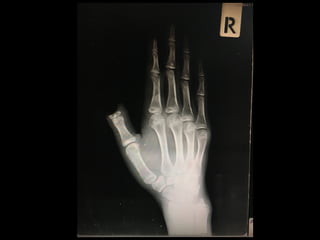

• ต้องส่งตรวจอย่างน้อย 2 มุมมอง

• ต้องการดูตำแหน่งใดให้ตำแหน่งนั้นอยู่ตรงกลางแผ่น

ฟิล์ม

• บาดเจ็บที่นิ้ว ต้องส่งตรวจภาพถ่ายที่นิ้ว ไม่ใช่มือ

• Right thumb AP, lateral

• ต้องส่งตรวจอย่างน้อย 2มุมมอง • ต้องการดูตำแหน่งใดให้ตำแหน่งนั้นอยู่ตรงกลางแผ่น ฟิล์ม • บาดเจ็บที่นิ้ว ต้องส่งตรวจภาพถ่ายที่นิ้ว ไม่ใช่มือ

• Right thumbAP, lateral